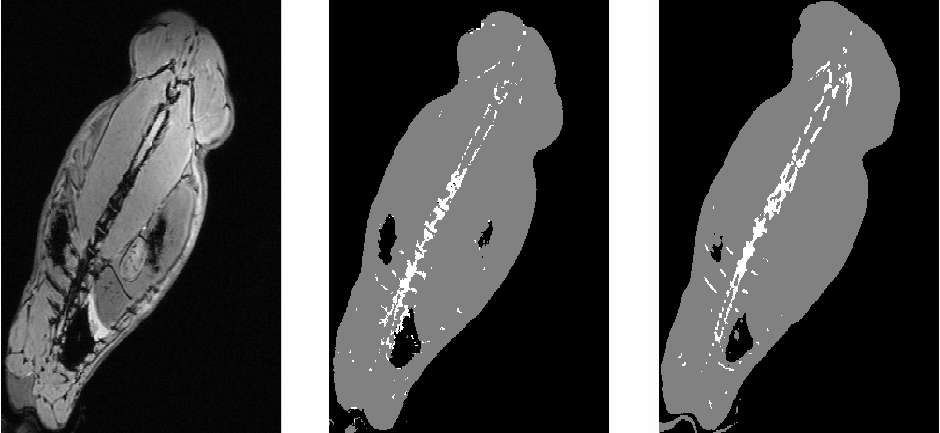

Another example, with slices of scans of a rabbit: In the CT images, the rabbit spine appears in white. The real CT scan does not correspond exactly to the MR scan because the rabbit was not set exactly in the same posture in the two scanners.